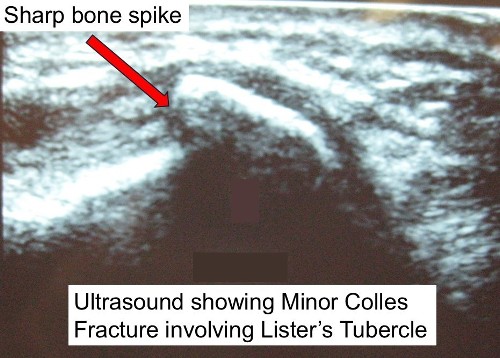

- In some patients, the fracture edges can be rough and they “saw” their way through the EPL tendon.

- This applies particularly when the fracture involves Lister’s tubercle – a prominence on the back of the radius around which the EPL changes direction

- The tendon may wear down and rupture, usually weeks – years after the fracture.